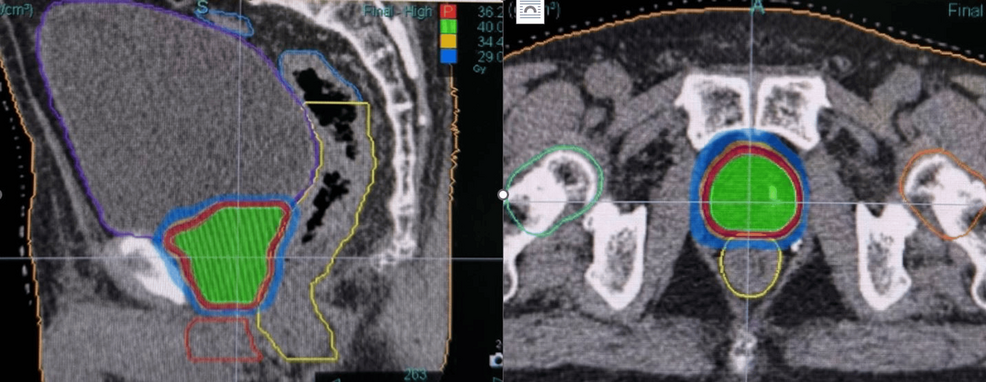

Example dose distribution for ultra-hypofractionated prostate cancer treatment

TreatmentSBRT with 36.25 Gy in 5 fractions, using criteria adapted from the PACE-B trial. Daily helical kVCT using ClearRT® for initial patient setup via fiducial marker matching